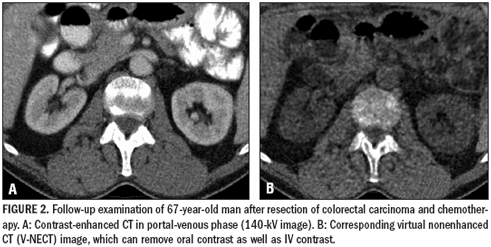

Dual-energy iodine maps cannot quantify dynamic parameters such as blood volume, blood flow, time-topeak enhancement, or mean transit time, as CT perfusion imaging can. The technique can, however, help to discern lesions with contrast uptake from those without and help monitor the effects of chemotherapy (Figures 2 to 5).

Iodine information can also be subtracted from CT data to produce virtual nonenhanced CT images. V-NECT and contrast-enhanced CT images are exactly comparable, but V-NECT requires just one CT scan, not two. The total radiation dose to the patient is consequently lower. The disadvantage of this approach is that V-NECT images have a limited field-of-view, and image quality is reduced compared with genuine unenhanced CT.